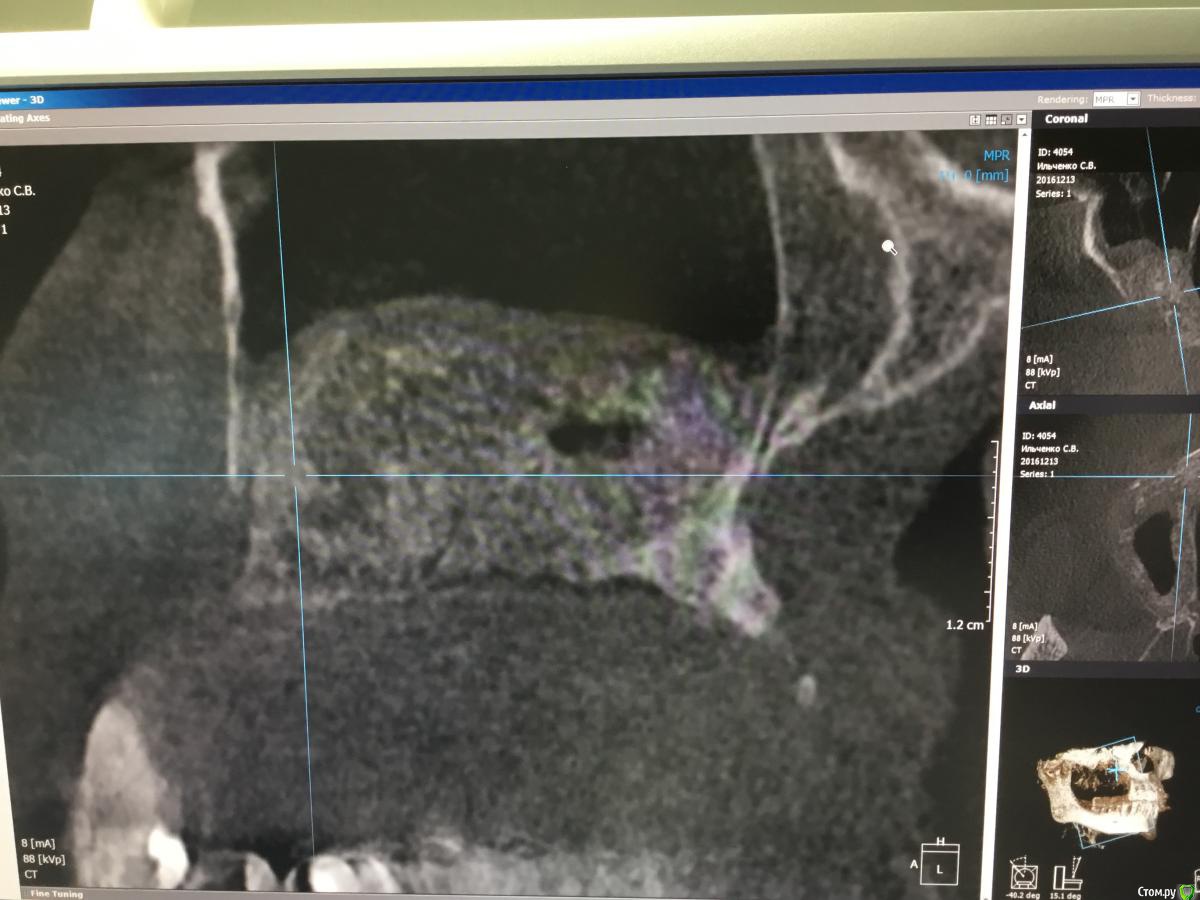

Bier Опубликовано 17 января, 2017 Автор Поделиться Опубликовано 17 января, 2017 7 мес, скорее расслоение, был бы разрыв, все бы в пазуху улетело. Ссылка на комментарий

gum Опубликовано 17 января, 2017 Поделиться Опубликовано 17 января, 2017 Если остальная часть материала оссифицировалась, то может быть, раскрыть, вычистить не сформировавшийся материал, установить имплантат (фиксация апикально в сформированную кость) и добавить костный материал в пустоту и под мембрану и все, кортикалка со всех сторон сохранена, воспаления нет, через окно прозондируете плотность материала. Как думаете возможен такой вариант? 1 Ссылка на комментарий

Bier Опубликовано 17 января, 2017 Автор Поделиться Опубликовано 17 января, 2017 как думаете, почему не весь графт отработал? На установке болтов окно после синуса "окостенелое" было?потому что произошла неполная отслойка слизистой пазухи во время операции. Она подвернулась или расслоилась. 1 Ссылка на комментарий

voff Опубликовано 26 января, 2017 Поделиться Опубликовано 26 января, 2017 синус в синусе Ссылка на комментарий